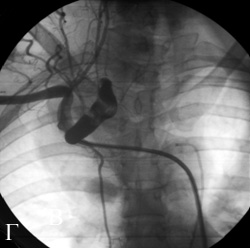

В полости аневризмы произвели раскрытие дистального отдела окклюдера с последующим низведением к границе проксимального отдела аневризматического мешка и интактной правой позвоночной артерии. Выполнялась ангиография, которая подтвердила правильное расположение окклюдера в полости аневризмы и наличие незначительного резидуального сброса крови через каркас устройства. Затем произвели раскрытие остальной части окклюдера. После имплантации окклюдера выполнили контрольную ангиографию, которая показала отсутствие антеградного заполнения полости аневризмы и наличие незначительного сброса крови через каркас устройства. Наличие резидуального сброса через каркас окклюдера не свидетельствует о неполном закрытии дефекта, так как процесс тромбообразования на устройстве может занимать несколько дней. Затем произвели отцепление окклюдера от катетера- толкателя (рис.7).

Рис.7 Закрытие аневризмы имплантацией устройства «Amplatzer» для закрытия открытого артериального протока .

Г) ангиограмма левой позвоночной артерии после операции